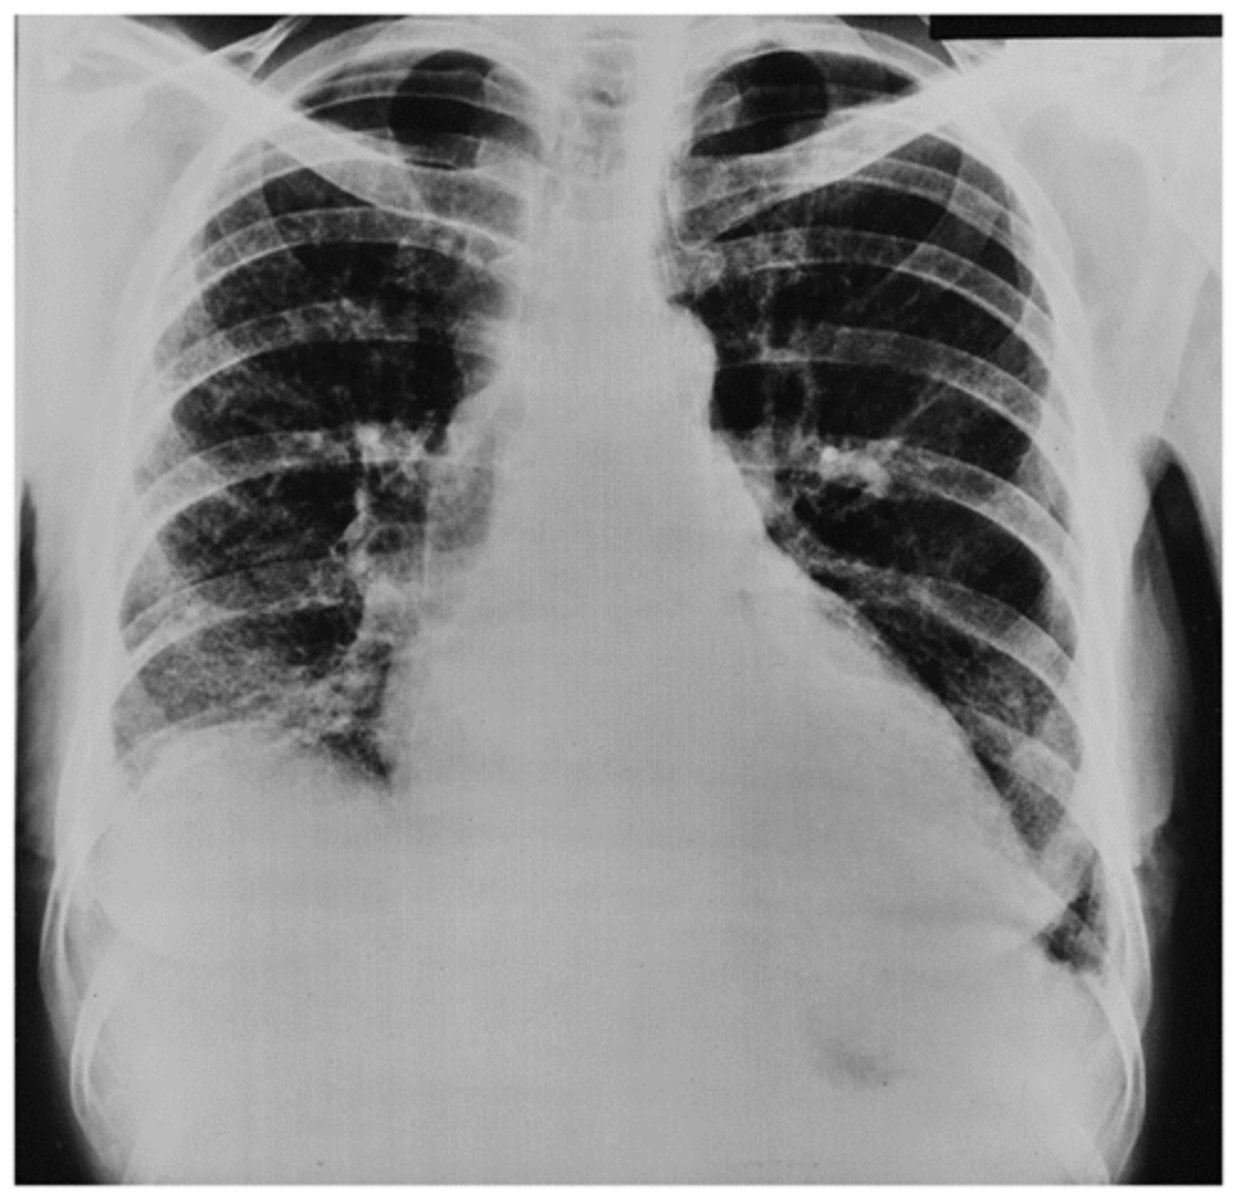

Interstitial Fibrosis ("honey combing" in the bases)

Interpretation?